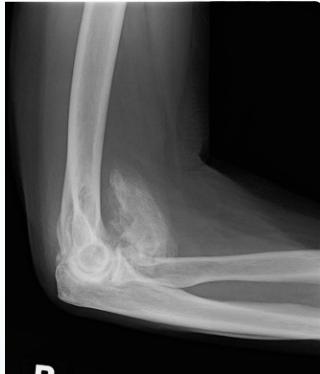

X-rays

- Which bone, and which site in bone?

- Solitary or multiple?

- Bone forming or bone eating?

- Margins: well-defined or ill-defined?

- Calcifications in the lesion?

- Is cortex eroded or destroyed?

- Is there periosteal new bone formation?

- Soft tissue extension?